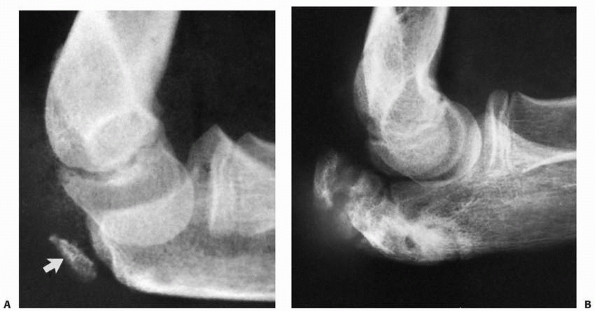

![]() |

FIGURE 11-35 Radioulnar synostosis. A.

Surgical intervention with wire fixation was necessary for a satisfactory reduction in this patient who had a totally displaced radial neck fracture. B. Six weeks after surgery, there was evidence of a proximal radioulnar synostosis. C. Radiograph taken 6 months after reduction shows a solid synostosis with anterior displacement of the proximal radius. (Courtesy of R. E. King, MD.) |